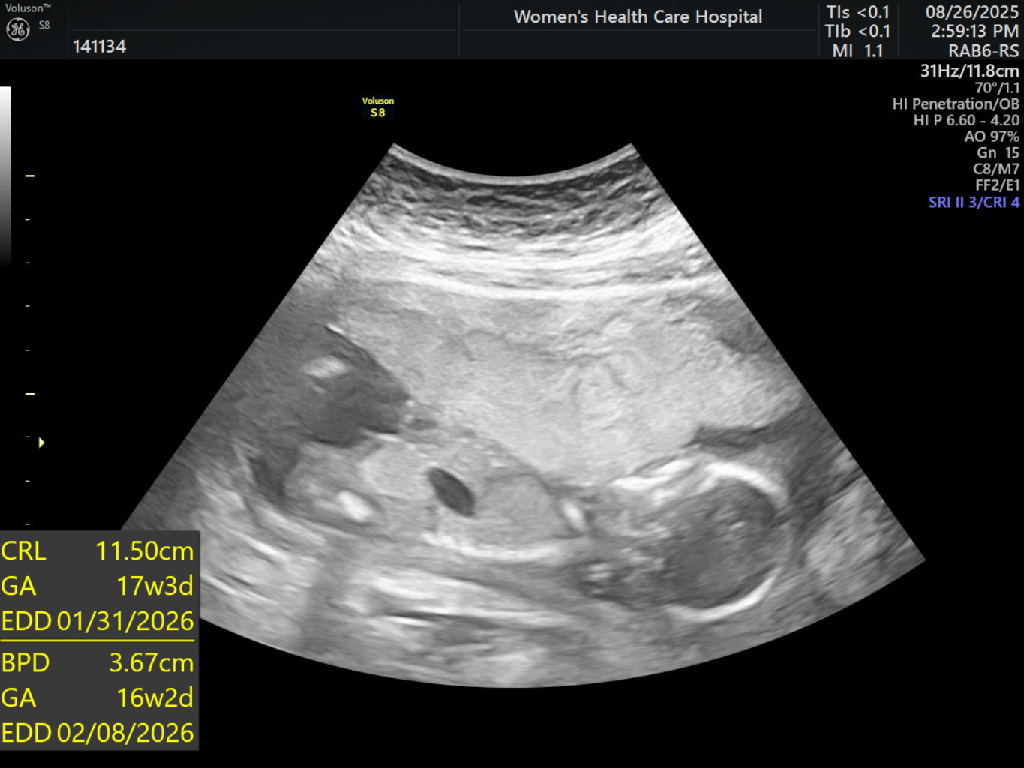

我知道報告不會顯示性別告知我們,那醫生會知道性別嘛?

我有驗nipt也是拿到報告當天做產檢(16週),醫生就有主動詢問是否要知道性別或是需要保密

醫生還是有照超音波給我們看說應該是男生女生

想說是不是醫生有知道報告確認了才會問我們😆